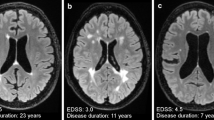

Diffusion tensor imaging (DTI) is a diffusion-weighted MRI method that measures brain tissue microstructure exploiting the properties of water diffusion. Using the measures obtained with this method, it is possible to calculate the magnitude of diffusion, reflected by mean diffusivity (MD), diffusion anisotropy, which is a measure of tissue organization, generally expressed as fractional anisotropy (FA), axial diffusivity (AD) and radial diffusivity (RD), with the latter two items being measures of axonal integrity and myelin integrity, respectively (Fig. 1) [36].

The FA within T2 lesions is usually decreased and the MD usually increased in comparison with those of the surrounding NAWM [37]. An overlap between MD and FA maps and T2 lesion distribution has been demonstrated in most MS phenotypes [38], with the exception of PP-MS patients, in whom there is a discrepancy between regional WM diffusivity changes and T2-visible focal lesions [39]. The absence of any overlap in PP-MS between FA maps and T2 lesions [38] support the hypothesis that axonal damage and T2 lesions are partially independent.

WM diffusion abnormalities are more pronounced in patients with SP-MS than in those with RR-MS [38, 40]. The greater increase in diffusivity in SP-MS than in other phenotypes is presumably caused by a combination of axonal loss and tissue destruction processes with inflammatory events [40]. The high degree of axonal degeneration in such patients is confirmed by the widespread decrease in FA, not only within lesions but also in the NAWM [38].

Although widespread diffusivity changes have been detected in patients with PP-MS in comparison with healthy controls, with increases in MD, RD and AD and decreases in FA [38, 41], the NAWM is affected to a lesser degree in PP-MS patients than in SP-MS patients [38, 42], probably owing to the more pronounced inflammation present in SP-MS than in PP-MS. Diffusion-based MRI parameters have been used to assess the role of natalizumab in SP-MS, with the results revealing a significant increase in FA in the NAWM and in AD and RD in T2 lesions after 60 weeks of treatment [31].